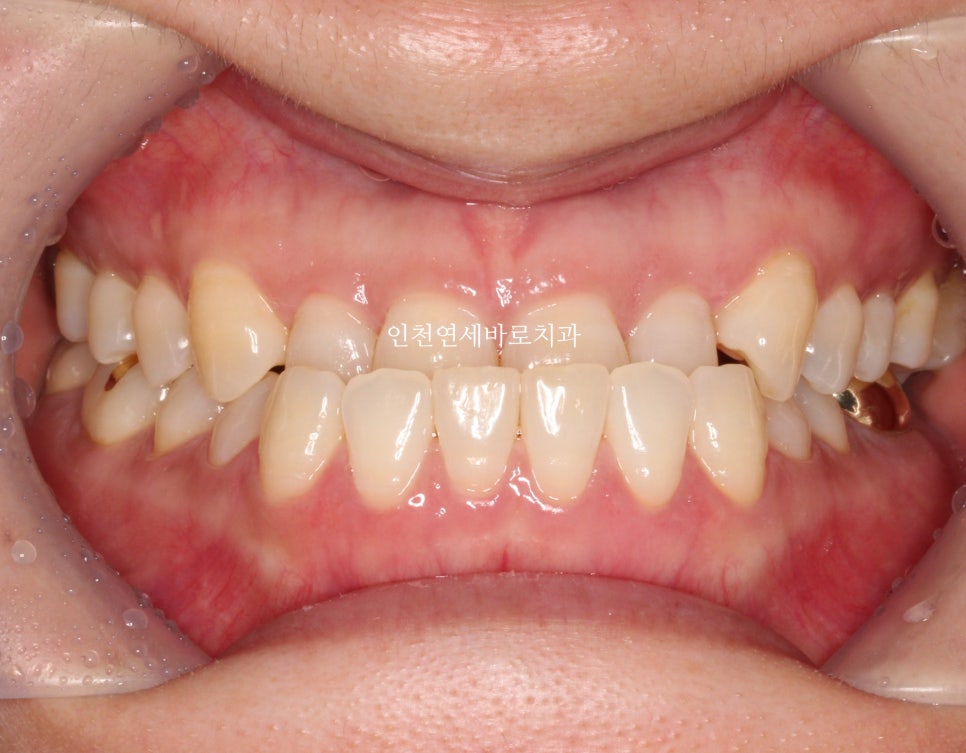

치료 완료 후 결과

치료기간은 조금 길게 걸렸지만 앞니 관계는 예쁘게 마무리

교합도 잘 마무리 되었고, 현재는 화살표 부분의 임플란트를 완성하기 위해 기다리는 중입니다.